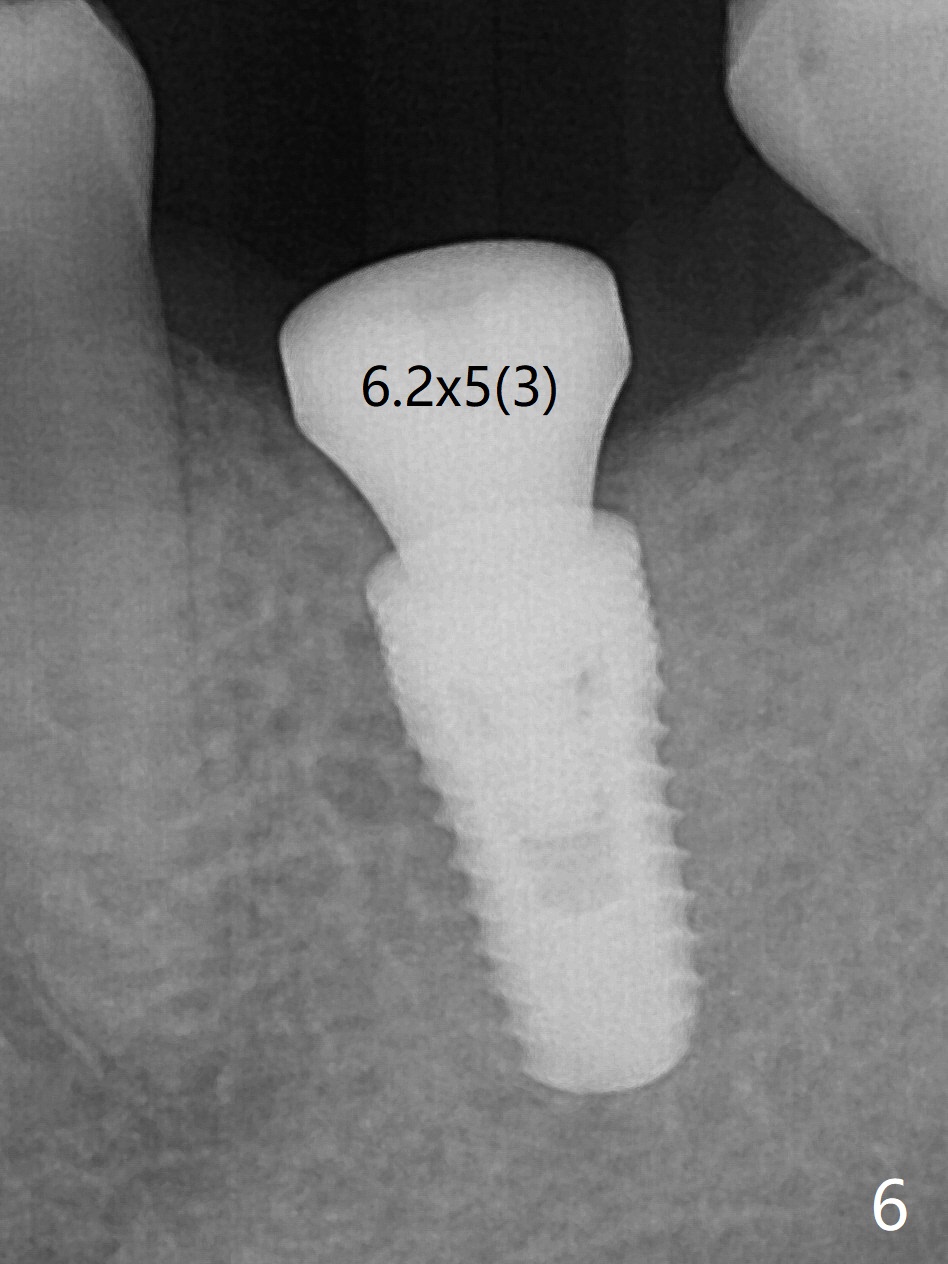

50岁男,左下6牙槽骨宽,但是骨密度低。开始使用导板和小钻头,植体(5x10毫米)扭力大,改用正常钻头,扭力仍高,使用功螺纹后,扭力~35Ncm;使用6毫米profile drill后,放置6x4(2)毫米愈合基台,后者好像与近中牙槽嵴接触(图一:*)。取出基台不顺利,接着放置5x5(3)毫米基台,无法拧紧,取出时,把植体带出来。最后把植体推入钻洞,没有任何扭力,放置愈合帽和Osteogen Plug,缝合(图二,三),牙周敷料,但愿能愈合。在骨质密度低时,放置不合适基台(太宽,太短),可能造成植体松动,脱落,失败。术后十二天牙周敷料脱落,伤口正在愈合(图四(曾经使用环形刀))。术后四个月植体仿佛已经整合(图五),切开放置6.2x5(3)毫米愈合基台,好像与近中牙槽嵴接触太紧(图六)。12天后放置修复基台,似乎就位(图七),其实我们使用取模帽放置基台,非常容易,取模也方便。基台牙冠就位也容易(图八)。螺丝拧紧25Ncm/厂家建议35Ncm。